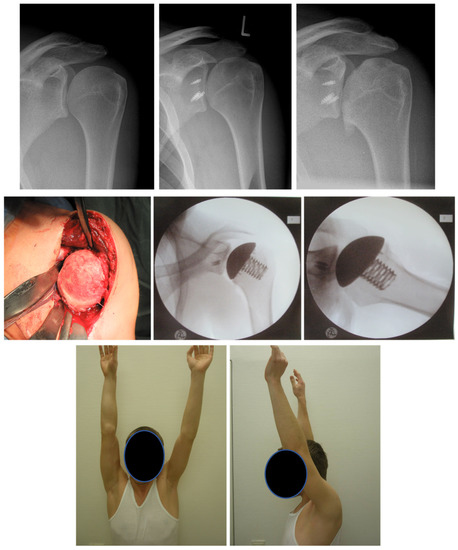

- Auffarth, A.; Schauer, J.; Matis, N.; Kofler, B.; Hitzl, W.; Resch, H. The J-Bone Graft for Anatomical Glenoid Reconstruction in Recurrent Posttraumatic Anterior Shoulder Dislocation. Am. J. Sports Med. 2008, 36, 638–647. [Google Scholar] [CrossRef] [PubMed]

- Moroder, P.; Plachel, F.; Becker, J.; Schulz, E.; Abdic, S.; Haas, M.; Resch, H.; Auffarth, A. Clinical and Radiological Long-Term Results After Implant-Free, Autologous, Iliac Crest Bone Graft Procedure for the Treatment of Anterior Shoulder Instability. Am. J. Sports Med. 2018, 46, 2975–2980. [Google Scholar] [CrossRef] [PubMed]

- Tauber, M.; Moursy, M.; Eppel, M.; Koller, H.; Resch, H. Arthroscopic Screw Fixation of Large Anterior Glenoid Fractures. Knee Surg. Sports Traumatol. Arthrosc. 2008, 16, 326–332. [Google Scholar] [CrossRef]